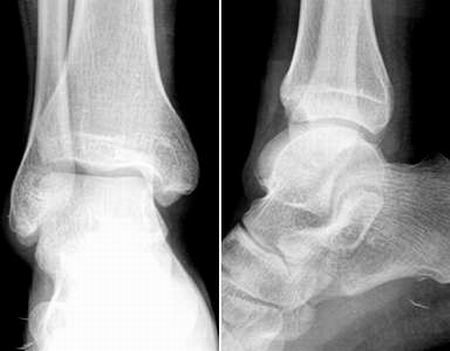

男,22y,小时候扭伤踝关节,现有时隐痛麻木,活动自如,其他正常。

踝部骨质及关节均未见异常.[跟距桥?]

距跟关节不对呀,有跟骨轴位片吗?

距骨形态怪怪的,踝关节半脱位?

此例踝关节构成骨及关节间隙未见明显异常.

跟骨下方软组织内的密度增高影是干扰影象吗?

跟骨下方软组织条状密影 异物待排